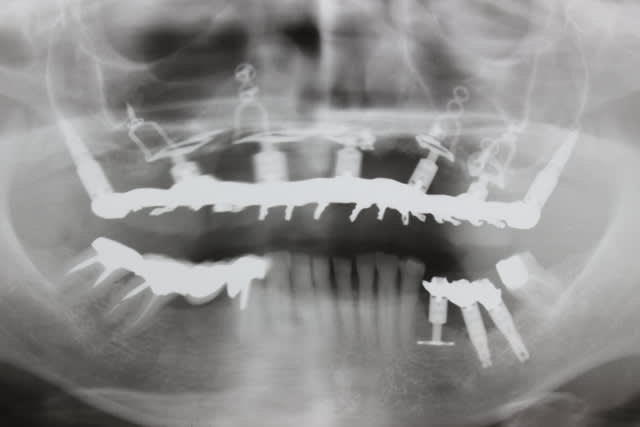

Les plaques existent depuis environ une dizaine d années

Je suis un des tous premiers à en avoir posé en dehors de GS puisqu à l époque il m en a confié une pour poser à la mandibule chez une patiente où je n avais pas pu poser un monodisk

J ai posé cette plaque en quais totalement enfoui à l époque : elle tjs là totalement indolore, bien sonore comme un cylindre

Je vais te filer qques photos d une patiente opérée voici 3 ans avec du nano et des plaques rien que l aspect de la muqueuse te montrera que tout ça est sain et ossifié